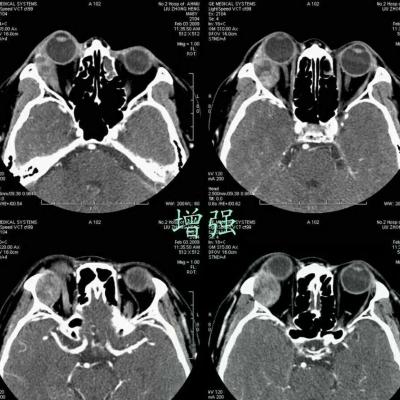

女,54岁,头痛头晕月余,无眼部症状及视力异常。 影像表现:右侧眼球后方占位病变,考虑海绵状血管瘤可能性大,鉴别:视神经鞘瘤、脑膜瘤及炎性假瘤。 病例点评:眼眶内血管瘤是较常见的良性肿瘤,其中以海绵状血管瘤最常见。可发生于任何年龄,主要表现为眼球突出及偏位,在低头或哭泣时可有突眼加重。可经眶缘触及具有压缩性的肿块。视力损害多较缓慢。肿块大多位于肌锥内,其次为肌锥外,平扫呈边界清楚的圆形、卵圆形或分叶状肿块,增强扫描呈缓慢进行性显著强化为其特征性表现。